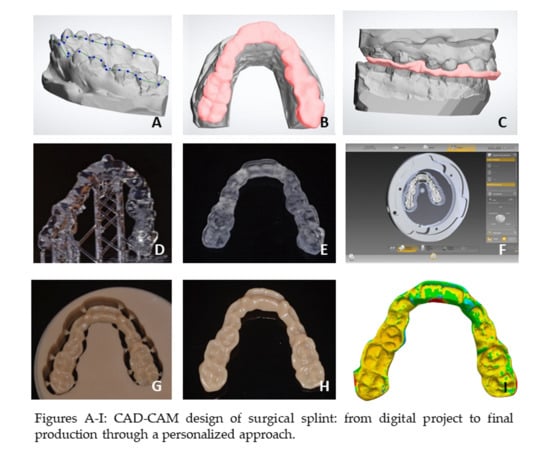

2. Materials and Methods

3. Results